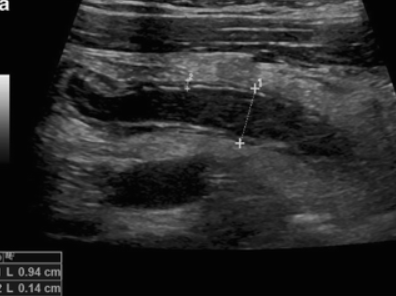

Regular stomach